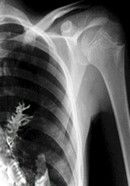

Pacientul a ajuns la spital acuzand dureri ingrozitoare si tuse cu sange, iar medicii au fost convinsi in urma radiografiei ca este vorba despre cancer pulmonar. "Am fost 100% siguri ca este vorba despre o tumoare. Am vazut sute de tumori pana acum, iar in urma radiografiei se vedea conturata imaginea unei tumori. De aceea am decis sa-l operam urgent", explica dr. Vladimir Kamashev, medicul care a efectuat interventia chirurgicala.Dupa operatie, chirurgul a analizat fragmentul de tesut prelevat in timpul biopsiei si a fost uimit sa descopere un bradut care a crescut, cel mai probabil, dintr-o samanta inhalata de pacient, spun medicii. Acum, barbatul de 28 de ani se simte bine si este in afara oricarui pericol.